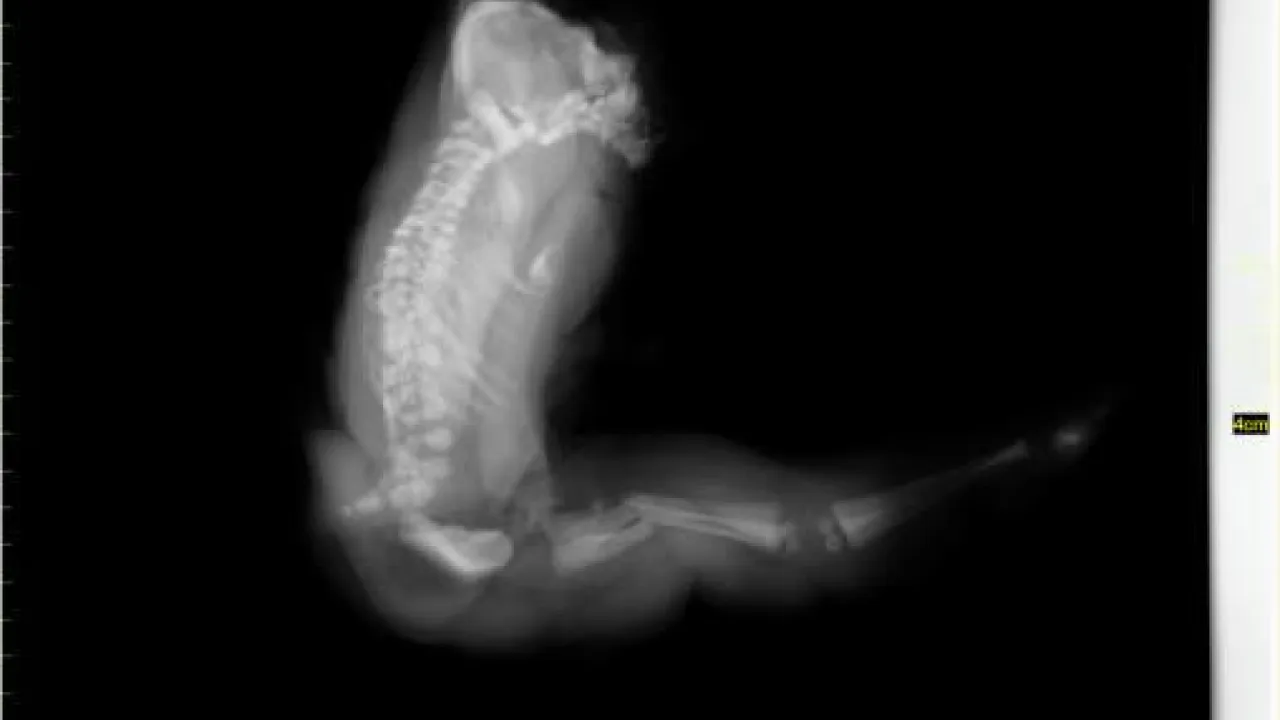

Skeleton and body morphology, Twin reversed arterial profusion sequence

Skeleton, Twin reversed arterial profusion sequence